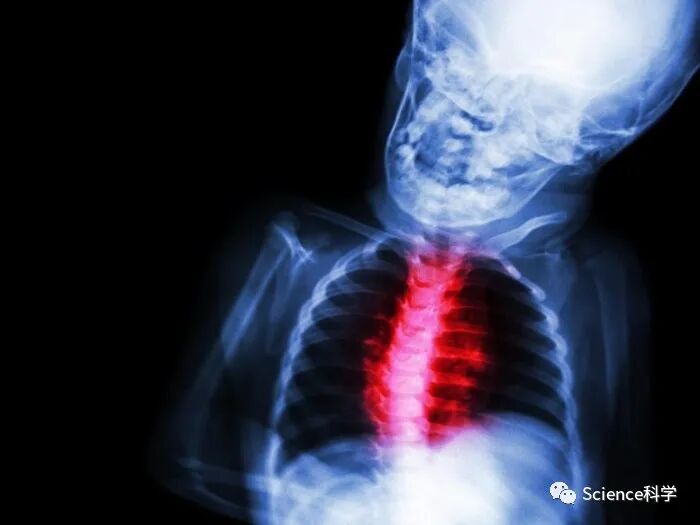

研究发现患有COVID-19相关多系统炎症综合征的儿童心脏功能恢复得很快

(2022年1月19日)发表在《美国心脏协会杂志》上的新研究,患COVID-19相关的多系统炎症综合征(MIS-C)的儿童通常在三个月内就可以恢复心脏功能,该杂志是美国心脏协会的一份开放性同行评审杂志。

MIS-C是在COVID-19大流行期间发现的一种新疾病,在接触COVID-19后约4至6周影响儿童。这种新疾病与川崎病有一些重叠的症状,然而,MIS-C与更严重的炎症有关。MIS-C可引起身体不同部位的炎症,包括心脏、肺部、肾脏和胃肠道器官。在整个美国和欧洲,大约80%-85%的MIS-C病例都涉及心脏的左心室。

这项研究详细说明了在三个月的随访期间发现的心血管并发症或损害,以评估MIS-C的短期影响。它还采用了较新的心脏测量方法,以评估与MIS-C有关的心脏功能。“strains”测试是一种更敏感的工具,可以检测出心脏的某个区域是否变形,或者在心脏收缩和放松时心脏功能是否有任何细微变化。

该研究发现:根据超声心动图成像,儿童左心室的收缩和舒张功能以及右心室的收缩功能在第一周内迅速改善,随后持续改善,到三个月时完全恢复正常。81%的患者在疾病的急性期失去了一些左心室的收缩功能,然而,到了第三和第四个月,收缩功能已经恢复正常。MIS-C并没有引起持久的冠状动脉异常。在最初的住院期间,7%的病人有一些心脏故障的证据,然而,到三个月的随访时,所有扫描都是正常的。